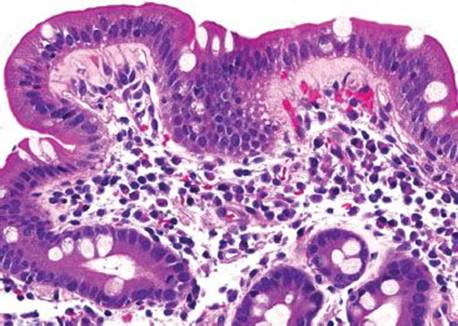

Figure 3.313 Acute duodenitis with gastric foveolar metaplasia and reactive epithelial change. The clinical impression of a mass lesion inspired deeper sections on this busy-appearing biopsy, although no histologic features of malignancy are readily apparent on this first level.

This case was received as “prominent ampulla, concerning for malignancy” (Fig. 3.313). The initial sections show duodenal mucosa with acute and chronic inflammation, gastric foveolar metaplasia, and marked reactive epithelial change (Fig. 3.313). Although these histologic features can account for a nodular clinical impression, deeper sections were pursued based on the clinical suspicion for malignancy. The first set of deeper sections were similarly concerning, but definitive malignancy was not seen. Deeper sections were repeated. And repeated. And repeated. In this case, the tissue block was exhausted and on the 38th level (!!!), clear lymphovascular invasion and infiltrating adenocarcinoma were seen (Figs. 3.314 and 3.315). When the histology does not fit the clinical scenario, consider deeper sections. When the deeper sections are not conclusive, consider repeat deeper sections or recommend rebiopsy (in this case, the patient was too unstable for a subsequent biopsy).